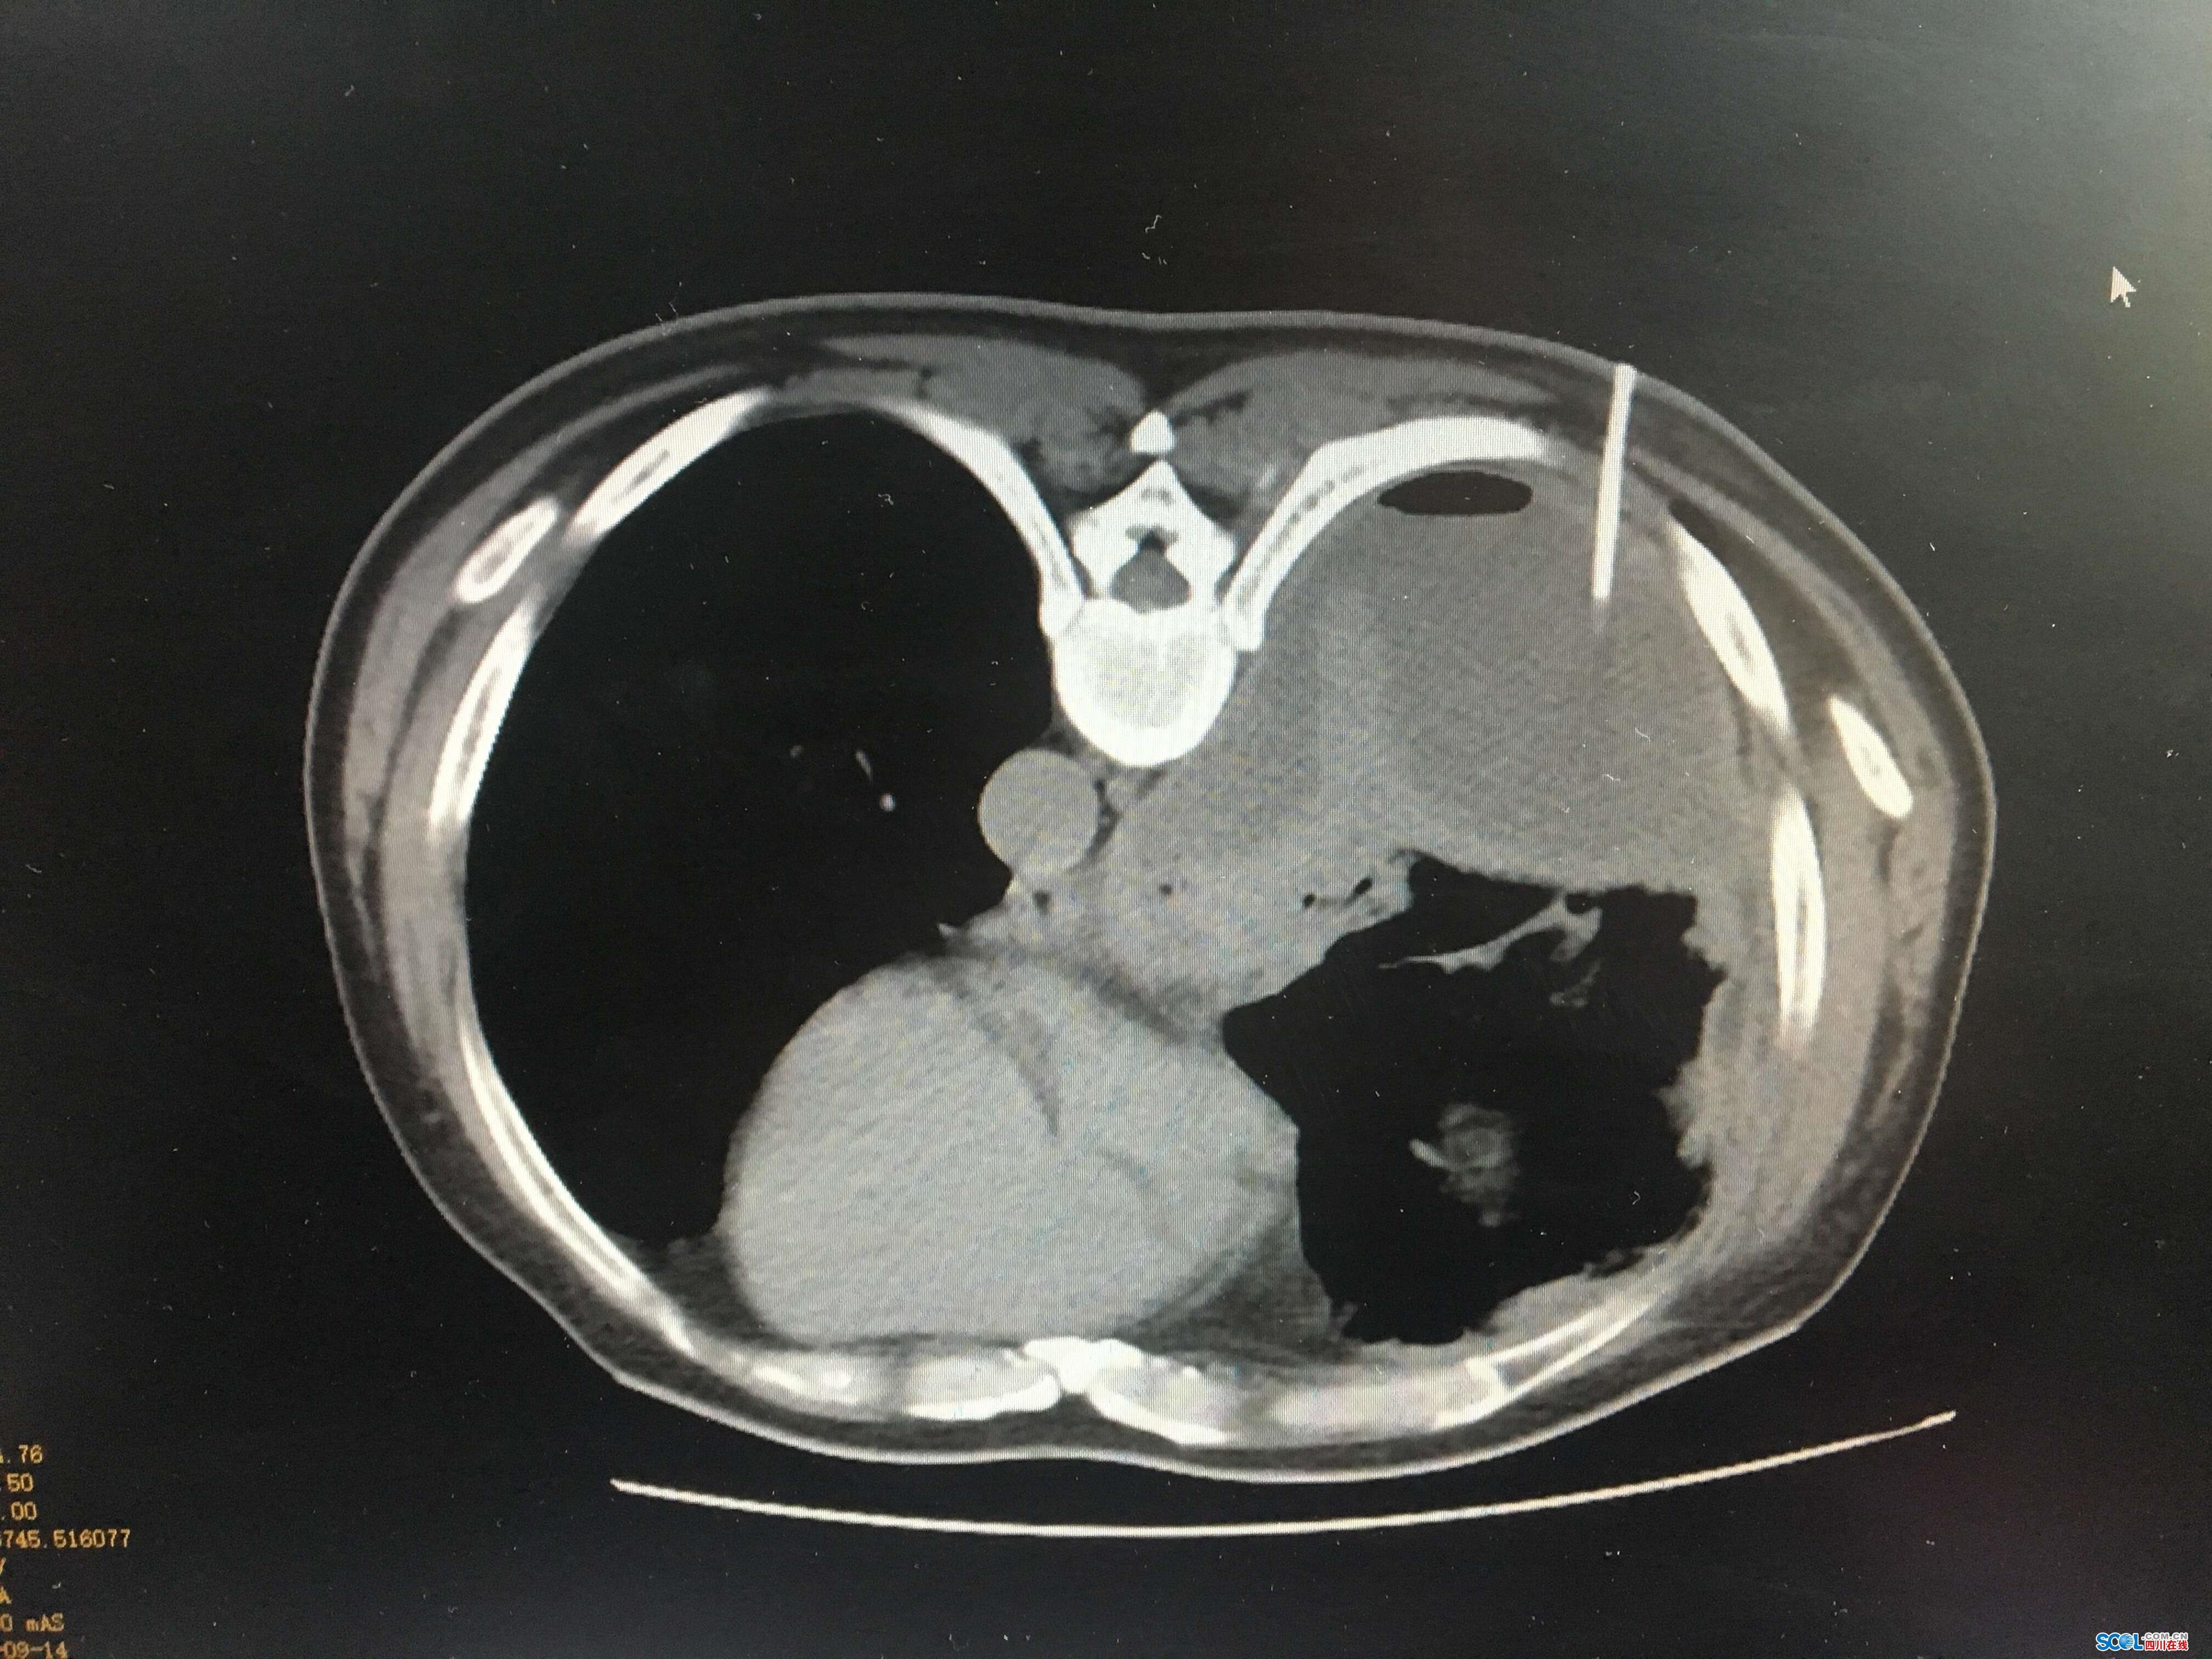

9月14日,呼吸与危重症医学科在CT引导下为该患者行胸膜穿刺术,顺利取出右侧增厚胸膜组织;抽出黄绿色黏稠带臭味的脓性胸腔积液;并安置了胸腔微创闭式引流管。此次操作为一次穿刺三项诊疗,谓之“一举三得”。整个过程不到20分钟,术中及术后患者无任何不适。目前患者已经引流出大量脓性胸腔积液,相关检查提示为感染性脓胸,经对症用药,现患者症状已明显减轻。(蔡维玲 张文莉)